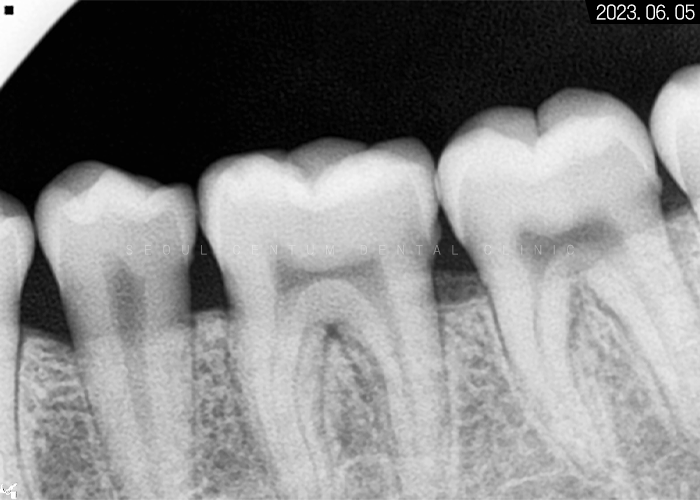

먼저 전체 치아 이동이 요구됐기 때문에

치면에 하나씩 브라켓을 모두 붙였으며

아래 와이어를 먼저 연결해서 압력 조절을 했고

그 후 위턱 치아에도 와이어를

일직선으로 연결해서 힘을 주었습니다.

특별히 정출된 곳이 없어서

엑스레이 사진에서 보면

바른 라인으로

와이어가 뻗어있는 것을 볼 수 있습니다.